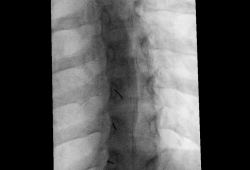

Tijdens de procedure

De behandeling gebeurt onder beeldgeleiding (röntgendoorlichting of echografie). U ligt op de buik, rug of zij, afhankelijk van de plaats van infiltratie. Via het infuus kan je een licht verdovend middel krijgen. De huid wordt ontsmet en lokaal verdoofd, waarna de arts de naald positioneert. Vervolgens wordt het medicijnmengsel ingespoten.